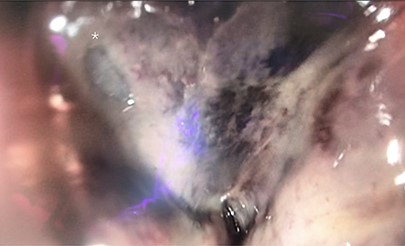

In retrospect, the patient reported anal pain during administration of a fleet enema 3 days prior. On inspection of the anus, there was a necrotic area leading into the anal canal. This finding of perianal trauma associated with the increasing evidence of sepsis led to a presumptive diagnosis of FG. CT scan (Fig. 2) demonstrated an area of hazing and small amounts of free gas within the perirectal tissue suggestive of a rectal perforation or FG. The patient was taken to theatre for an urgent intervention. The scrotum and perianal region required debridement of the affected soft tissue (Fig. 1). Sigmoidoscopy demonstrated circumferential necrosis of the lower portion of the rectum consistent with REI (Fig. 3). A decision was made to expectantly manage the rectal injury and perform a repeat sigmoidoscopy with the aim of preserving the rectum in lieu of an urgent rectal resection. The antibiotic regime was changed to meropenem, clindamycin and vancomycin. Tissue cultures from the debridement grew scant colonies of Pseudomonas aeruginosa and Bacteroides uniformis. The repeat sigmoidoscopy demonstrated stabilization of the rectal ischaemia. A diverting colostomy was created to assist in application and management of negative pressure dressings to the perineal wound (Fig. 4). He required 2 days of post-operative ICU support and over the next 2 weeks, symptoms and inflammatory markers returned to normal. An examination under anaesthesia performed 1 week later demonstrated interval improvement of the rectal mucosa with resolving necrosis. The patient was discharged after 3 weeks with no further dressings and the colostomy was reversed 3 months later.

Operative photo. The wound at final operative inspection was partially closed. A negative pressure wound management device was placed to the remaining defect. A diverting colostomy was created in order for the management device to be undisturbed, as the remaining defect was around the anus.